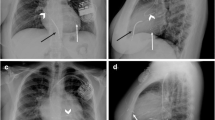

MR imaging–guided cardiac catheterization has become a clinical reality (Fig. 2), after years of technological development and preclinical/clinical testing [11, 71, 96]. There is a move for industry participation in the development of CMR-compatible cardiac catheters and devices specifically designed for CMR-guided cardiac intervention. Cardiac EP is the first field for which clinical grade device development is complete and in which human clinical trials are currently underway. Regarding congenital heart field, complex anatomy particularly requires wires and end-hole catheters with good steerability and torque to negotiate the bends of the relevant cardiac and vascular structures. Development needs to keep pace with the meticulous processes of regulatory approval of devices and also needs to be some verification in terms of the cost-effectiveness of these techniques and their role in improving patient outcomes. However, CMR-guided interventions in paediatric cardiology will continue to develop as a consequence of the continued striving for better anatomical and physiological data and avoidance of radiation. We predict that the next decade will see interventional MRI catheterization become a more widespread clinical reality.